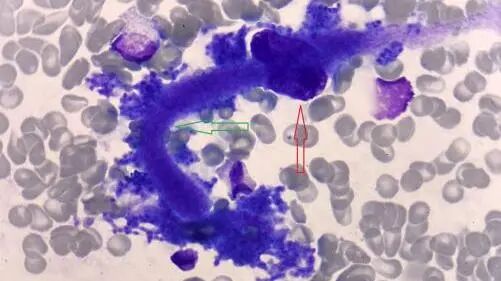

3.骨髓形态:嗜酸性粒细胞比值偏高,占6%(黑色箭头),可见侏儒状巨核细胞(红色箭头)及畸形血小板(绿色箭头),见图3。

图3 骨髓形态(黑色箭头:嗜酸性粒细胞;红色箭头:巨核细胞;绿色箭头:畸形血小板)瑞氏-姬姆萨染色(10*100)